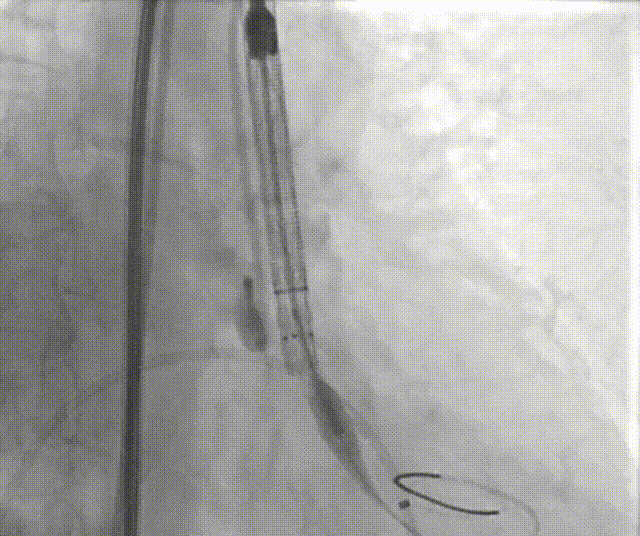

手术过程